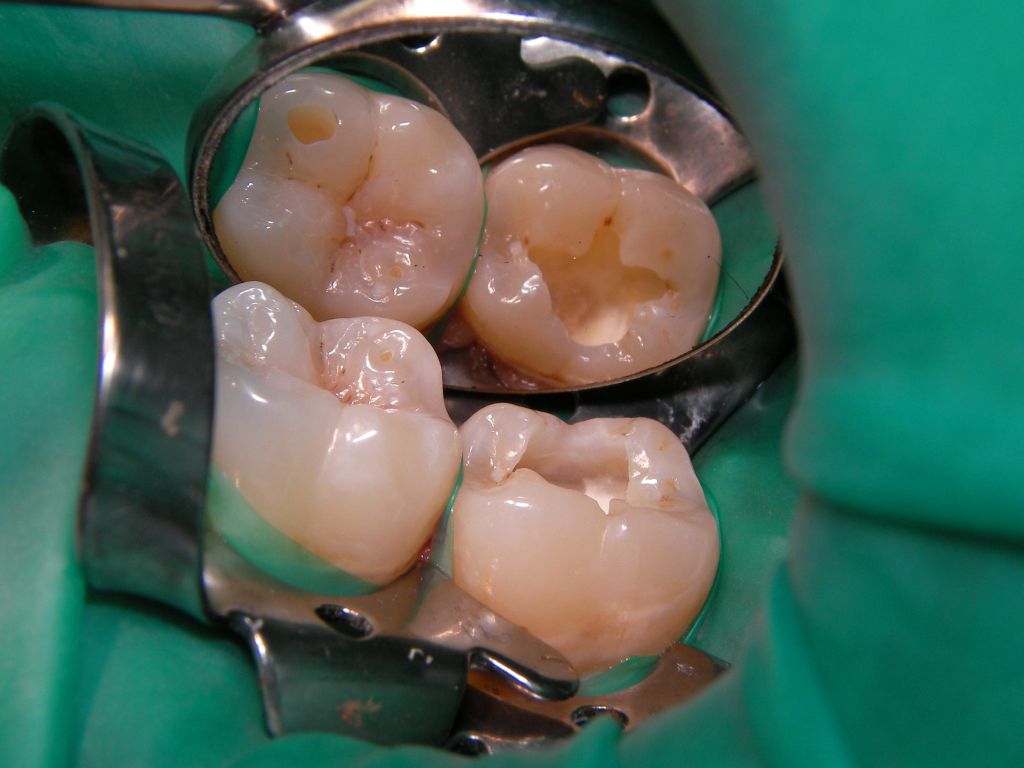

| Schließlich eine 22jährige, junge Dame, die trotz Aufklärung über die vermutlich etwas eingeschränkte Haltbarkeit eine weiße Kompositfüllung statt Amalgam wollte: | |||||||||||||||||||||||||||||||||||||||||||||||||||||||||||||||||||||||||

![]() | Am Ende waren es sogar 3, nicht nur 2 Füllungen (wer sieht die 3.?). Das grüne Latexgummi ist Kofferdam (=Spanngummi), der manchmal die Arbeit erleichtert, weil er den Speichel fernhält. Zuzahlung für die Kassenpatientin 2 * 30 . Mit Speichelfilm sind solche Füllungen im Alltag nicht mehr zu erkennen. |

![]() | |||||||||||||||||||||||||||||||||||||||||||||||||||||||||||||||||||||||